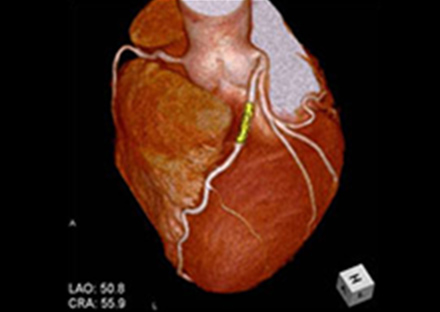

X線とコンピューターを利用して人体の断面画像を撮影する装置で、全身の臓器の形態診断に不可欠な存在となっています。当院のCT装置はエリアディテクターCTと呼ばれる最新の技術が用いられており、広範囲を短時間に撮影する事ができます。検出器1回転が0.275秒での超短時間ボリュームスキャンでスクリーニング検査から救急・精密検査まで、一度の撮影で多くの情報を得ることが可能です。得られた画像から脳血管や心臓血管・骨などの立体的(三次元)表示・解析も可能となっております。また、造影剤を使用することで、より詳しい検査を行う事も可能です。

当院はキャノンメディカルシステムズ主催「画論 ザ・ベストイメージ 2016」のCT AquilionONE部門で最優秀賞を獲得しました。